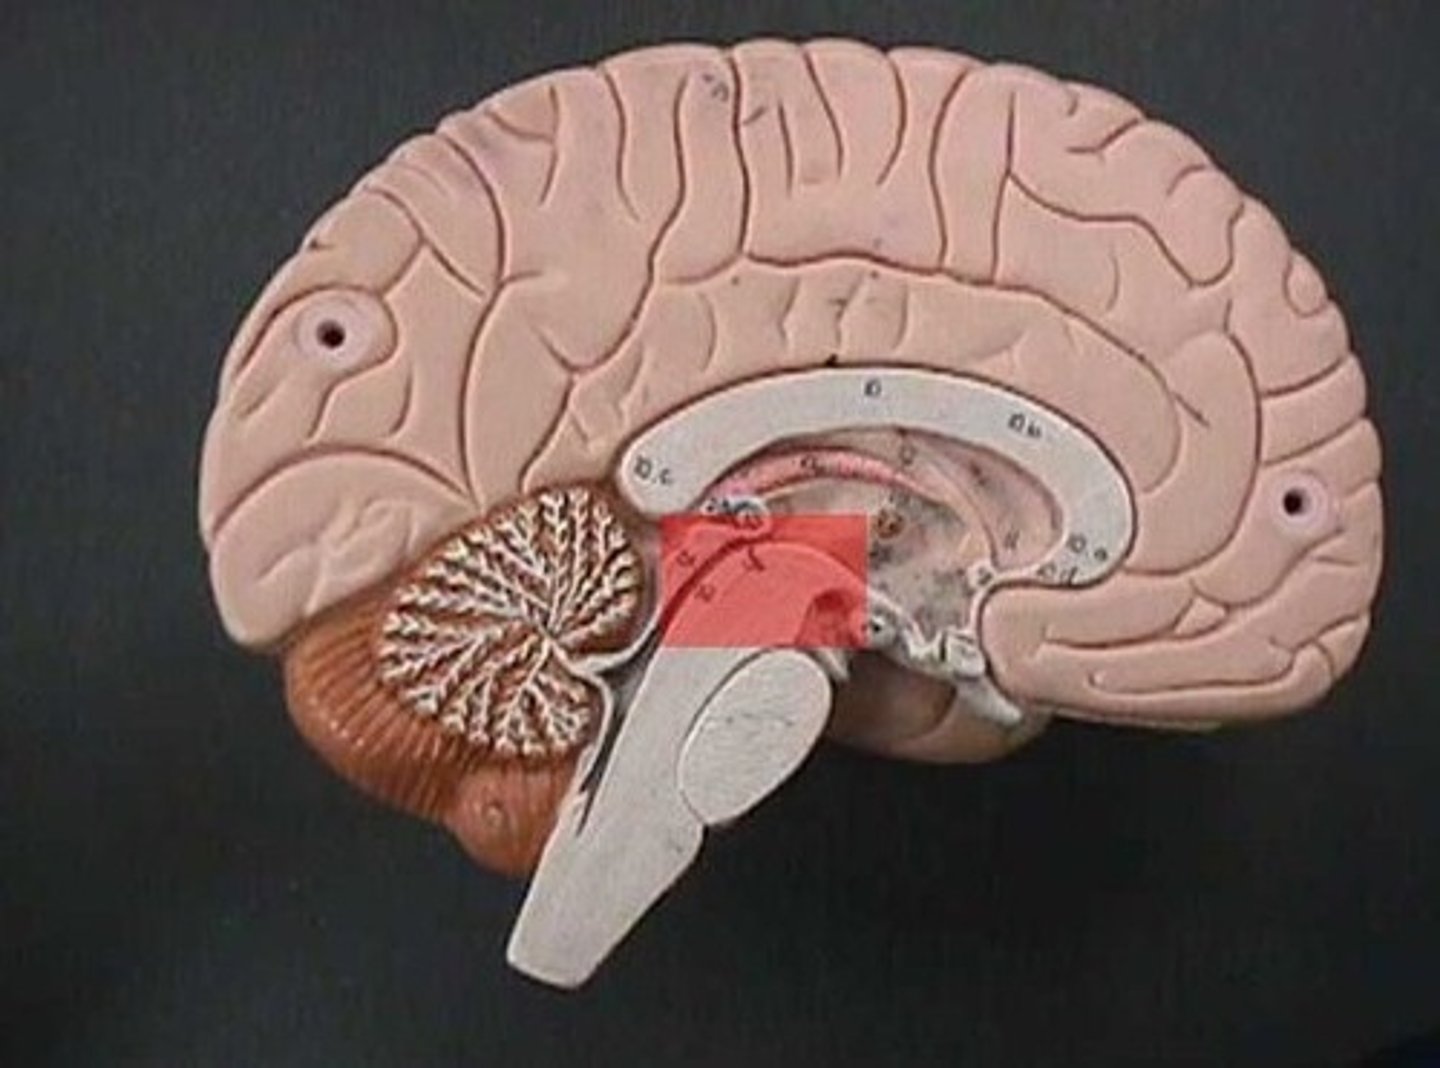

midbrain (mesencephalon)

corpora quadrigemina

superior colliculi

inferior colliculi

cerebral peduncles

between brainstem and thalamus

pons

medulla oblongata

cerebellum

arbor vitae

cerebral aqueduct (mesencephalic aqueduct)